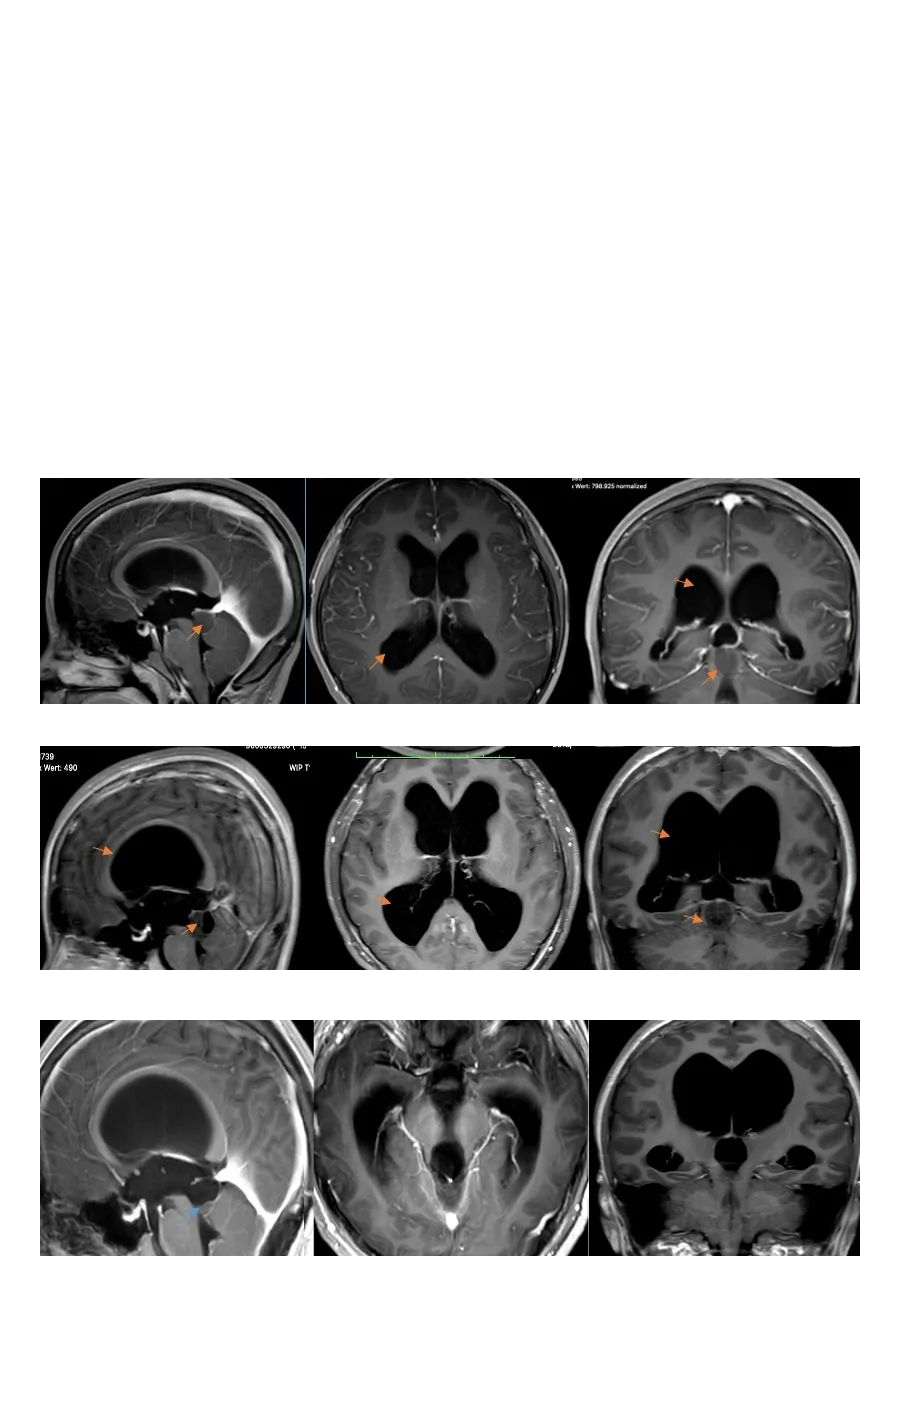

【脑干胶质瘤】脑干胶质瘤拖了2年、脑积水加重并压扁大脑,德国术后没有复发、无后遗症、迎战中考

2020年11月,14岁的小永因患脑干-中脑顶盖部位的毛细胞型星形细胞瘤住进医院,MRI影像检查发现松果体区占位伴幕上脑室扩张积水,病灶有明显强化生长迹象。小永父亲在医生朋友的下联系到INC德国巴特朗菲教授进行国际咨询咨询。巴教授表示,小永已有很明显的手术指征,如果能及时接受手术,脑脊液通道可以通过肿瘤的切除而得到恢复。教授凭以往的手术经验判断,可实现神经外科显微镜下手术近全切瘤,且手术风险很低。

收到巴教授的咨询意见回复后,小永父母决定带孩子赴德国接受巴教授的手术治疗。由于肿瘤基底部和脑干关系密切、紧邻小脑,术中教授在保全患者正常功能神经和脑干等重要脑组织的前提下,完成肿瘤近全切手术,术后无新发长期性后遗症。术后1年多回访时,小永父母表示孩子手术后恢复很好,经过康复治疗,现在已经可以正常生活和学习,并正在备战中考,为此感谢巴教授的治疗。